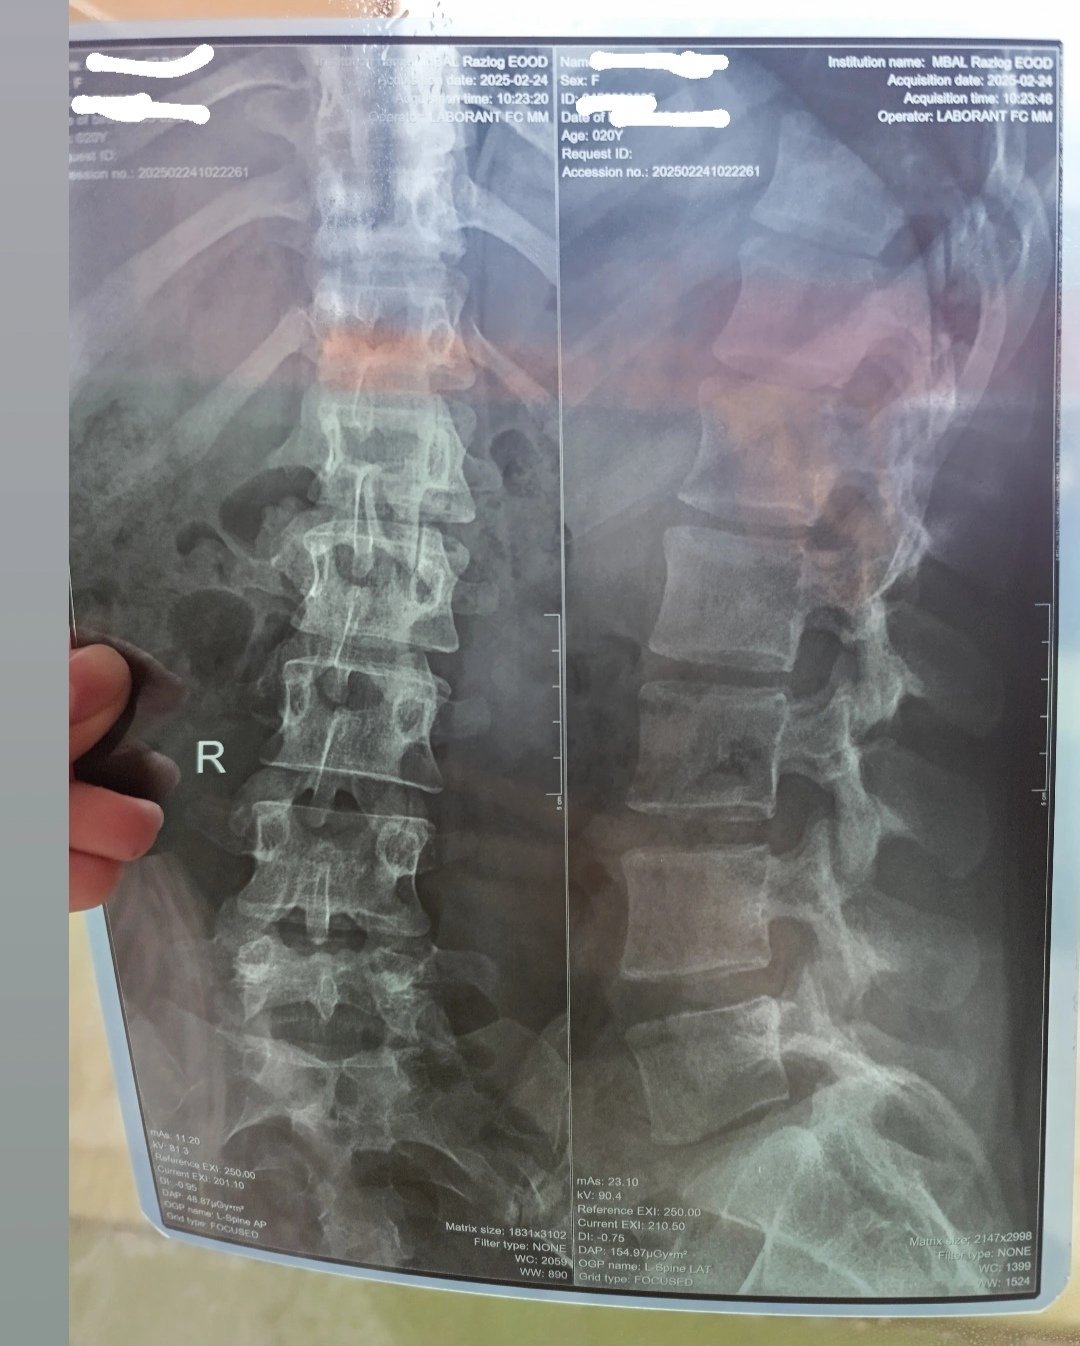

Здравейте д-р Георгиев. 4м след раждане имам ужасни болки в кръста, не мога да стоя седнала повече от 10 Мин, а ако съм наведена пак толкова горе-долу едвам се изправям. Направих снимка, но не знам към ортопед или невролог да се обърна. Ще се радвам ако успеете да я разчетете.

Много често след раждане се засилват болките в кръста и гърба. Както и се открива и сколиоза, както е при вас: ляво конвексна сколиоза около 6 гр.

- Започнете физиотерапия

- Започнете редовно спортуване

- Намалете натоварването